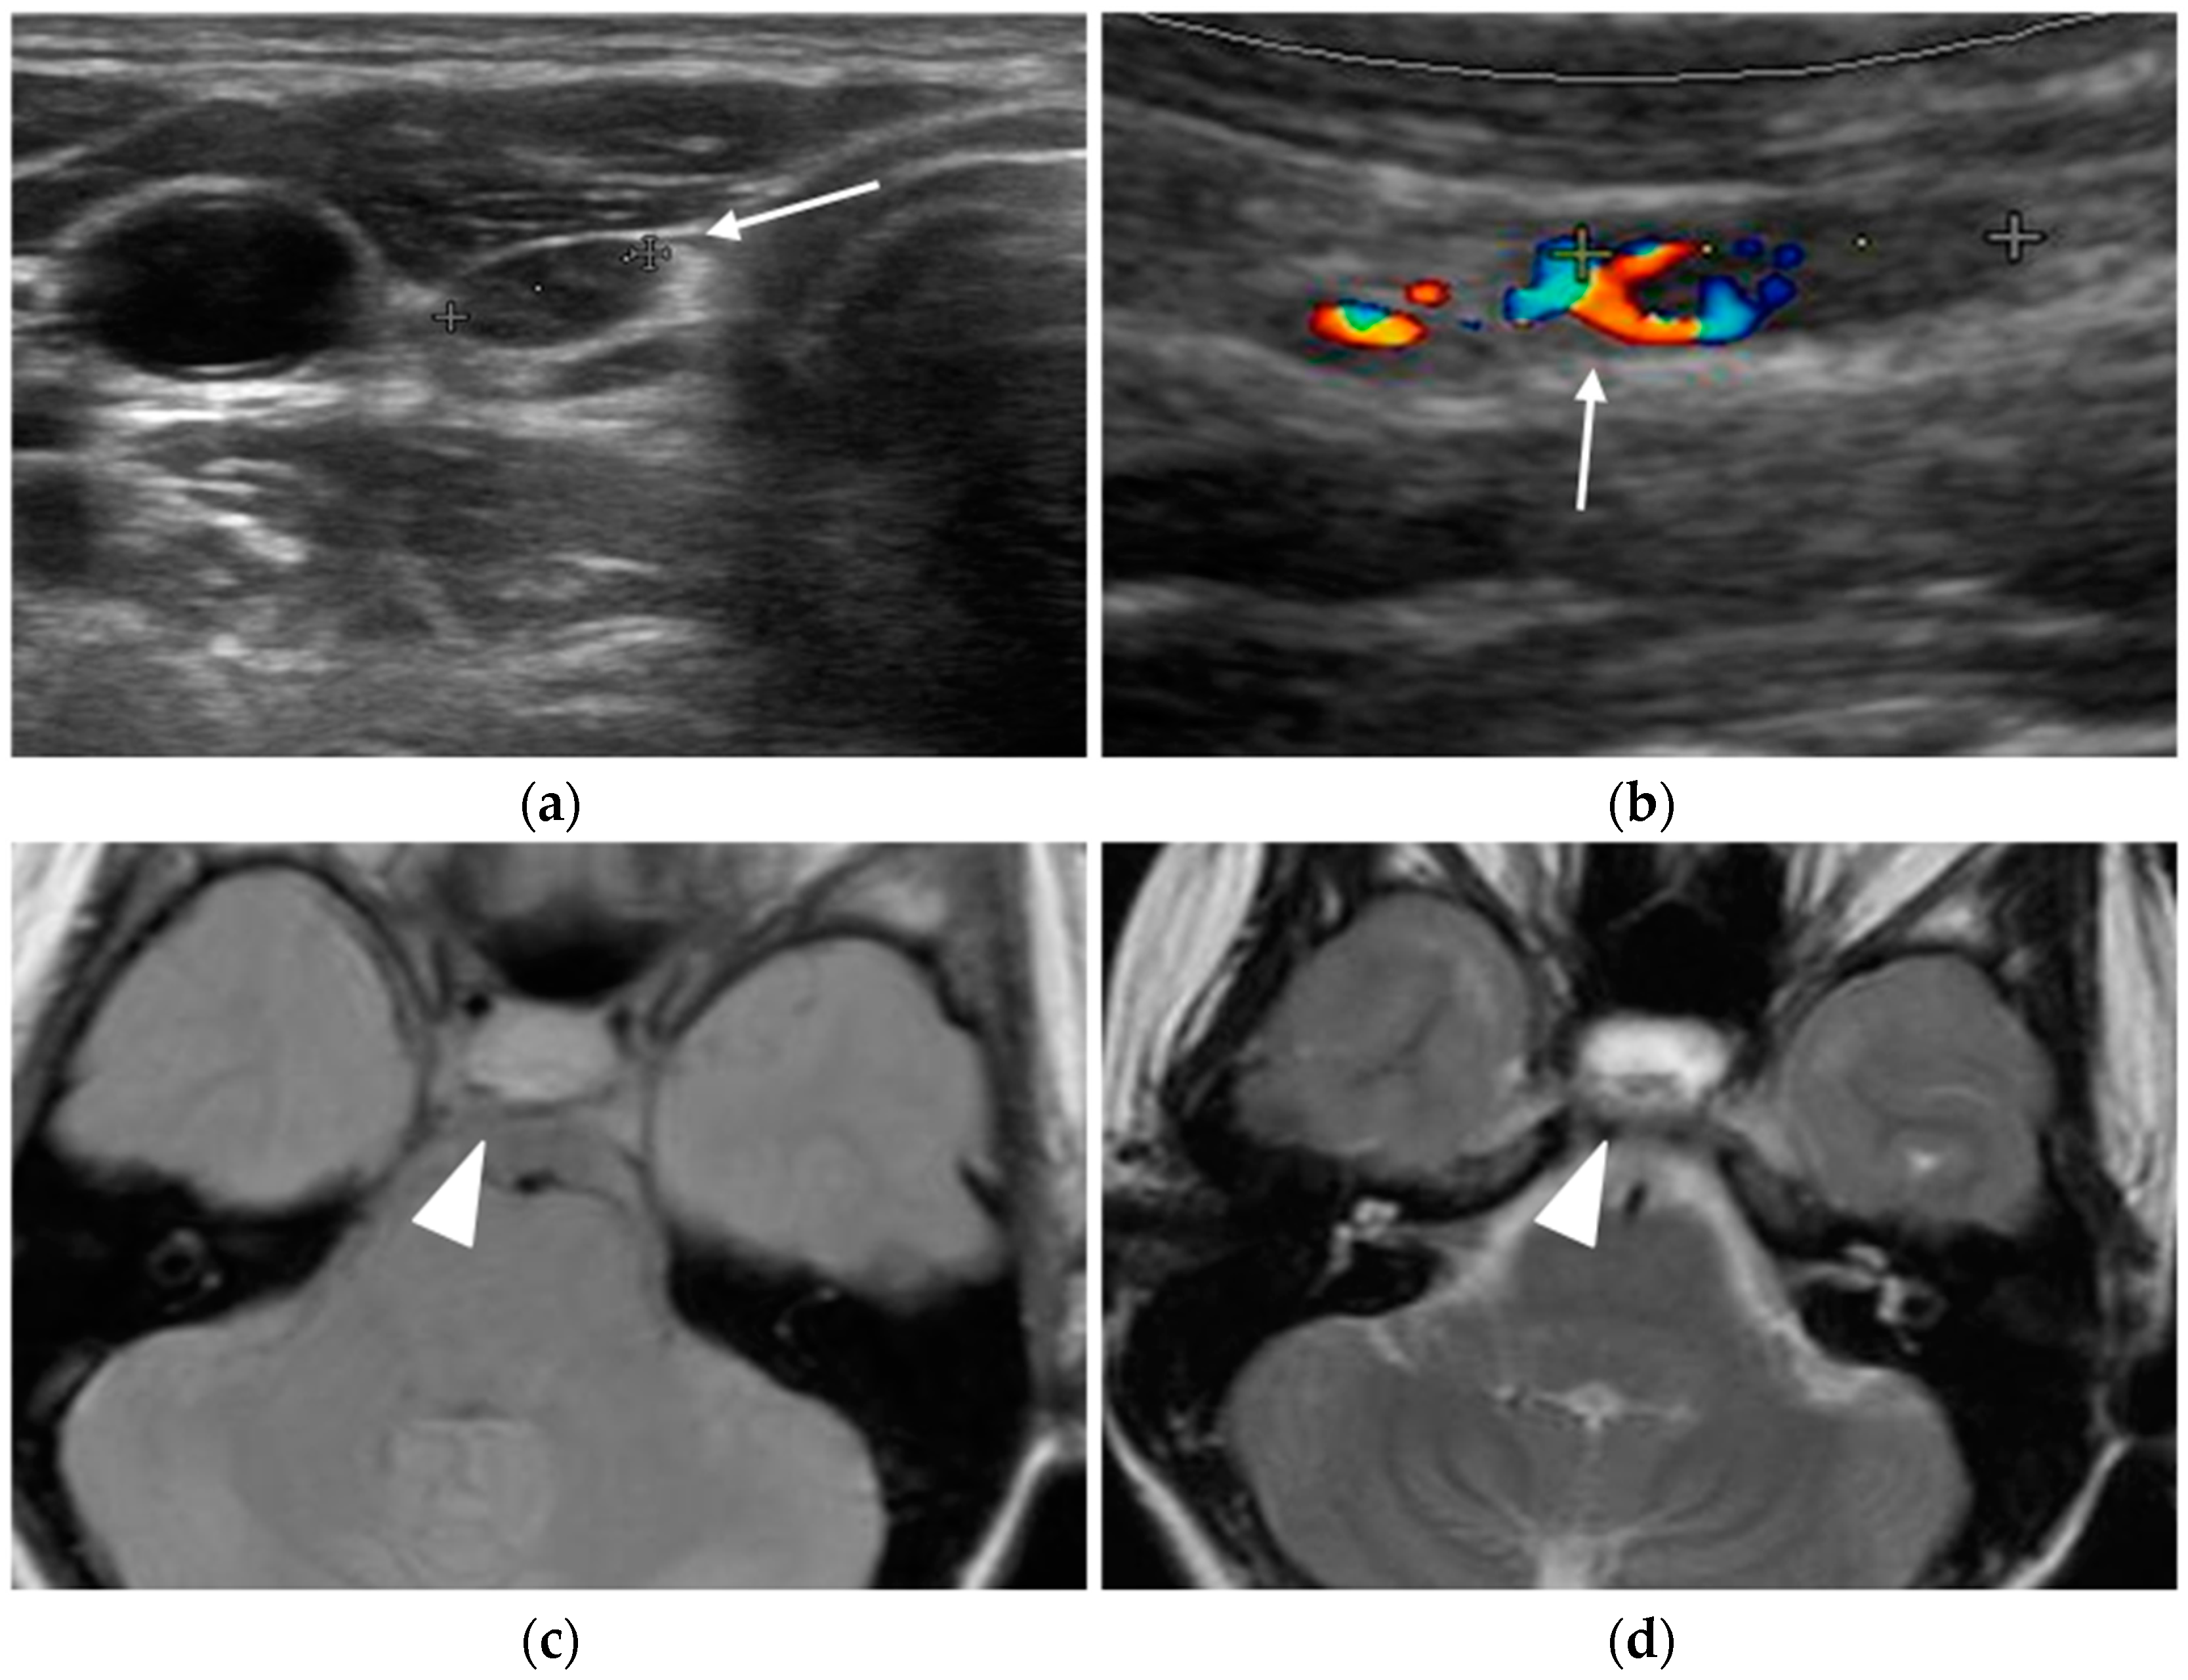

MRI

MRI is the gold standard imaging modality for diagnosing and following pituitary adenomas: its excellent soft tissue contrast helps characterize pituitary lesions and their relationship with surrounding structures, providing useful information for surgical planning.

The MRI protocol for investigating hypophyseal diseases includes small-field-of-view coronal and sagittal T1-weighted and T2-weighted sequences, focused on the sellar region, as well as coronal and sagittal T1-weighted sequences after intravenous contrast administration [49]. Dynamic post-contrast T1-weighted sequences may be helpful in the detection of microadenomas.

Adenomas are often isointense to the adjacent pituitary parenchyma in T1- and T2-weighted sequences. However, microadenomas can be slightly hyperintense on T2-weighted images and have a delayed enhancement compared to the background pituitary parenchyma (Figure 8). Some small microadenomas are not always visualized on imaging, and therefore it is important to acquire dynamic post-contrast sequences, as they increase the sensitivity in identifying the lesion, and to look for secondary signs, such as erosion of the sellar floor or focal convexity of the superior pituitary gland [17].

Figure 8.

Pituitary micro-prolactinoma. T1-weighted MR images before (a) and after (b) contrast administration showing a hypointense and low-enhancing nodule (arrow) in the anterior pituitary gland.

Pituitary macroadenomas can have a heterogeneous signal on unenhanced sequences due to solid, cystic, necrotic, and hemorrhagic areas. After contrast administration, macroadenomas typically show heterogeneous enhancement (Figure 9).